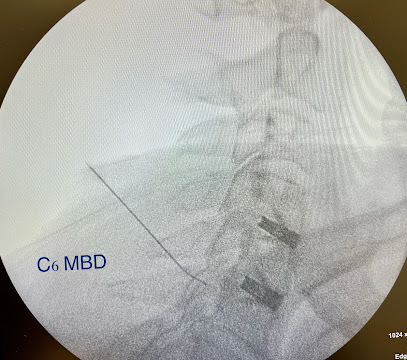

Dr. Manish Raj

طبيب إدارة الألم ,